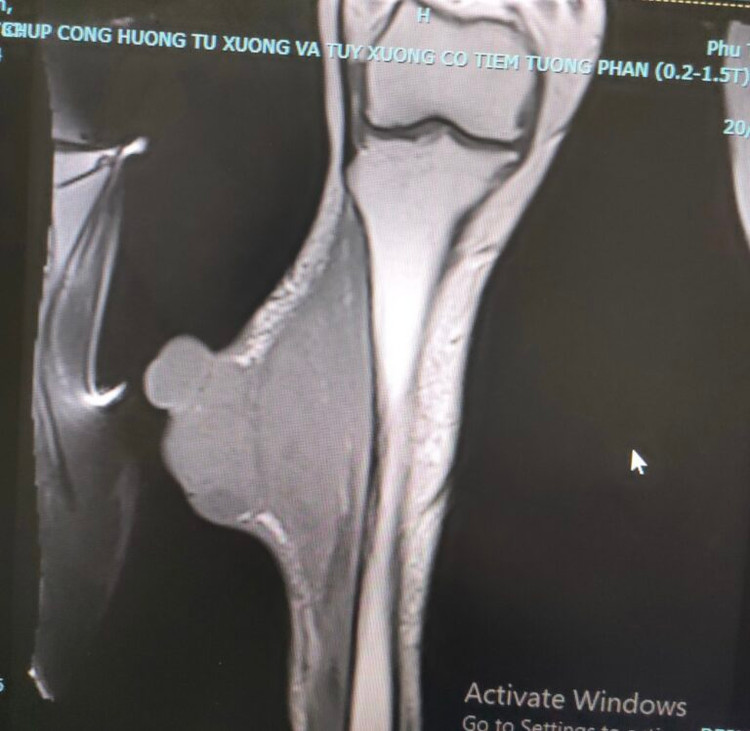

Hình ảnh khối u phát triển với kích thước lớn ở chân người bệnhHình ảnh khối u phát triển với kích thước lớn ở chân người bệnh

Khi vết thương có kích thước 15×10 cm gây đau nhức nhiều, không đáp ứng với thuốc giảm đau, người bệnh đã được đưa tới khám tại Bệnh viện K. Tại đây, người bệnh được làm sinh thiết và chẩn đoán xác định ung thư phần mềm giai đoạn IV có di căn hạch bẹn cùng bên và di căn phổi.

Hình ảnh khối u xâm lấnHình ảnh khối u xâm lấn